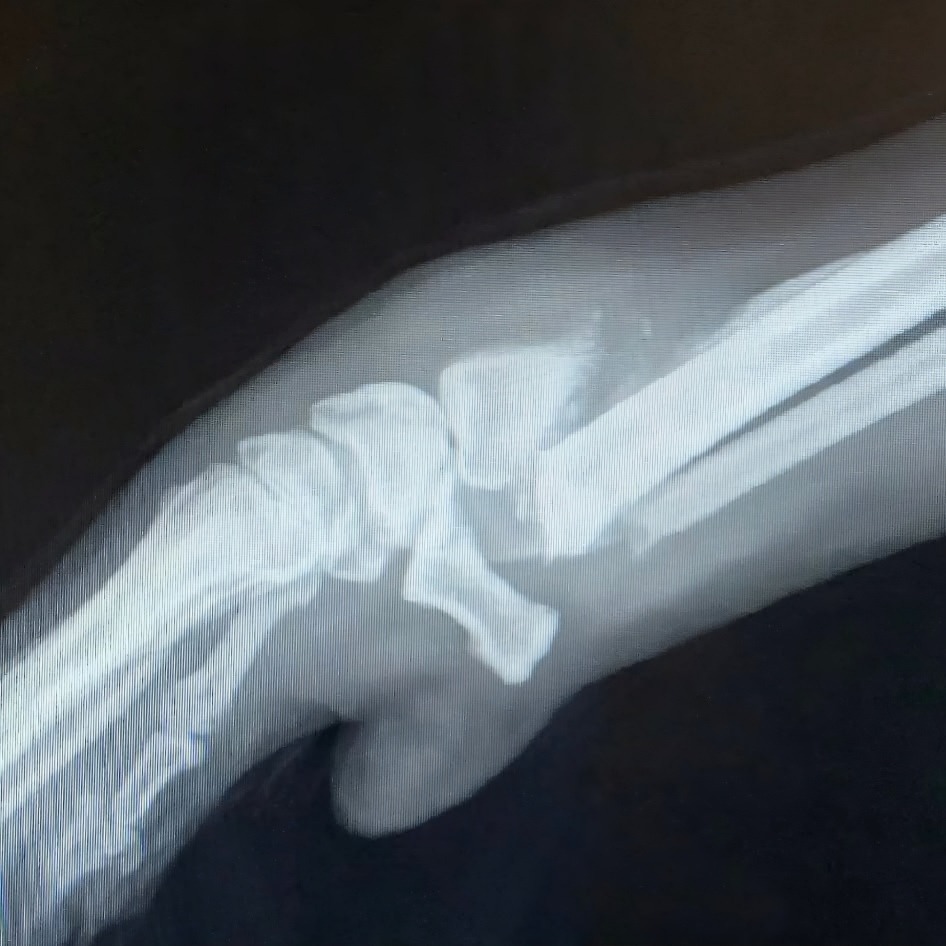

But after his adopter, Sheree, brought him home and followed up with their own veterinarian, the truth was far more serious. Imaging revealed that both his radius and ulna are completely broken.

Because of the severity of the injury, amputation was first presented as the only realistic option. But this is where love stepped in.